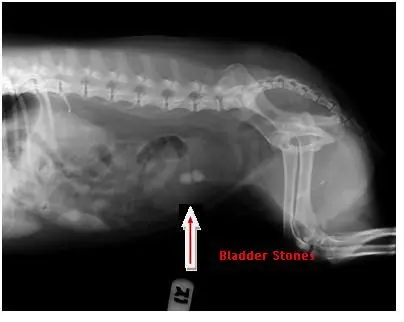

Radiographs help us in many ways.  They help diagnose broken bones, may show possible foreign bodies, bladder stones, masses, abnormalities of heart and lungs and so much more.  This can help pet owners see what is happening inside their animals and help them understand why certain treatment courses are then recommended.

Now it is your turn to give it a try:

Look at these x-rays and guess how they helped the veterinarian make the correct diagnosis.